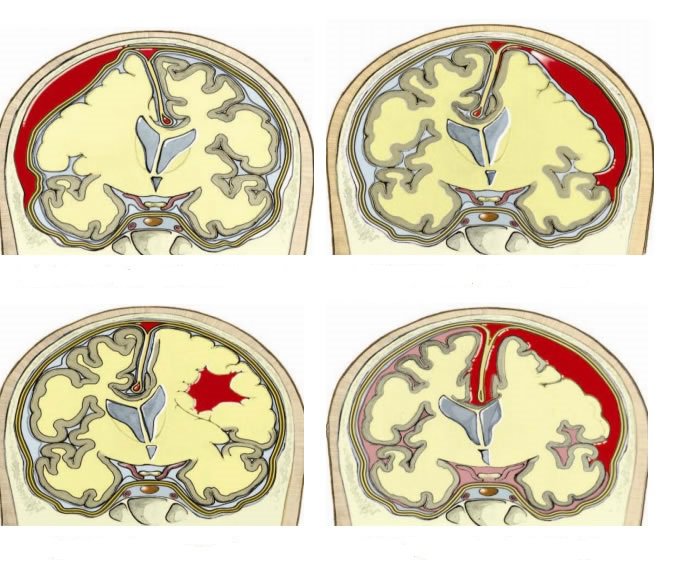

Chấn thương sọ não là tình trạng hộp sọ và não bị chấn thương do va chạm với các vật cứng. Trong một số trường hợp, hộp sọ bị một vật xuyên qua cũng có thể gọi là chấn thương sọ não.

Chấn thương sọ não để lại hậu quả ảnh hưởng đến các tế bào não. Trường hợp nặng có thể dẫn đến bầm tím, rách các mô não, chảy máu não và các tổn thương khác. Những hậu quả này có thể dẫn đến biến chứng và tử vong.